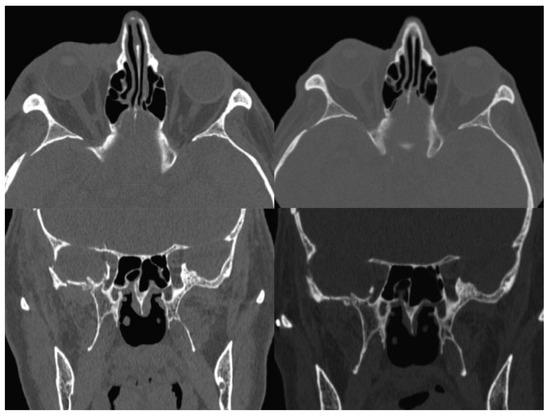

Immediate Reconstruction of Large Full-Thickness Segmental Anterior Maxillary Defect with Bone Transport

by Alberto Rocha Pereira, Nuno Montezuma, Luis Oliveira, Miguel Magalhães and José Rosa

Craniomaxillofac. Trauma Reconstr. 2016, 9(4), 305-312; https://doi.org/10.1055/s-0036-1592094 - 15 Sep 2016

Cited by 5

Abstract

Maxillary segmental defects are a reconstructive challenge particularly when the anterior arch is involved. Missing bone, mucosa, and teeth should be replaced; fistulae closure should be guaranteed by bone and mucosa continuity; stable functional occlusion should be achieved; and facial aesthetics restored. These [...] Read more.

Maxillary segmental defects are a reconstructive challenge particularly when the anterior arch is involved. Missing bone, mucosa, and teeth should be replaced; fistulae closure should be guaranteed by bone and mucosa continuity; stable functional occlusion should be achieved; and facial aesthetics restored. These defects resulting from tumor excisions, if left untreated, will cause additional problems related to interposed scar and collapse of lip and nose. Immediate reconstruction should avoid these problems and should be considered when safe tumor-free margins are obtained. This study describes the treatment of such a defect resulting from a myxoma excision, with trifocal distraction requiring only one additional surgery. Internal distractors were fixed bilaterally for transport of two segmental discs created by inverted L osteotomies at the same surgical time of tumor excision. A second surgery was performed after central contact between transport discs was achieved, for device removal and creation of a dynamic system to regenerate molding and compression-focus development. This was accomplished by internal fixation of one side and central fixation of a full-open distractor to act as compression device when reversely activated. Central perfect adaptation between transported segments and good-quality attached mucosa lining the alveolar crest were determinant to obtain a stable functional and aesthetic result. Full article

Show Figures

Figure 1